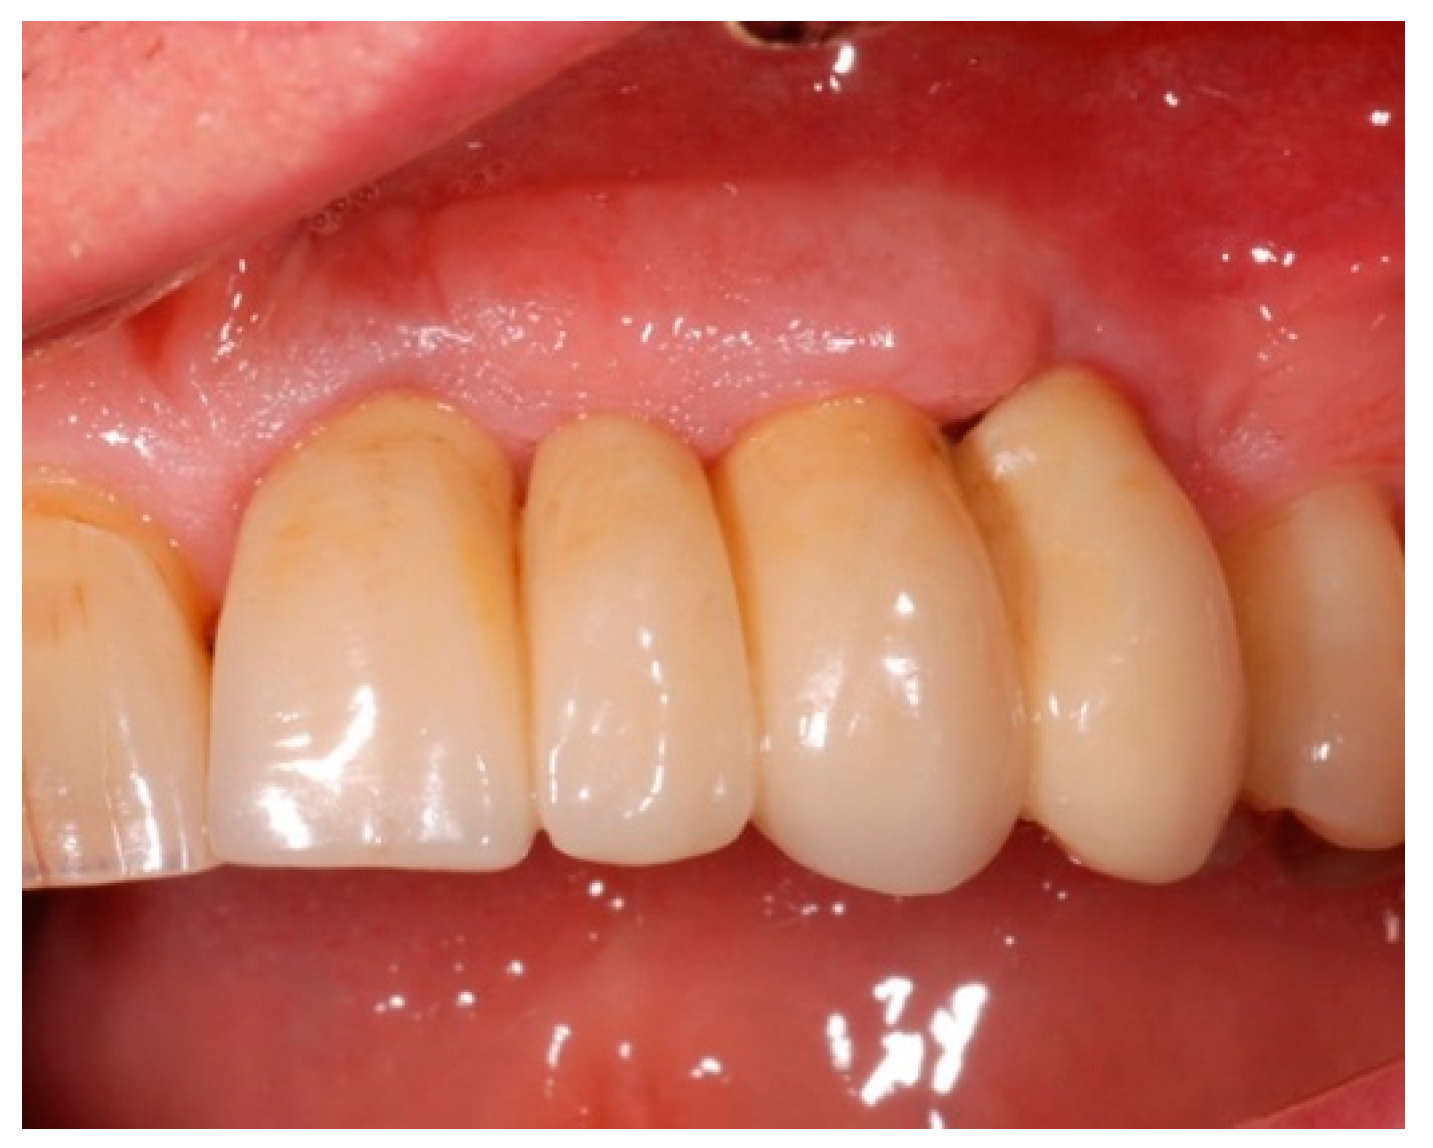

4.5. Test Substances and Administration